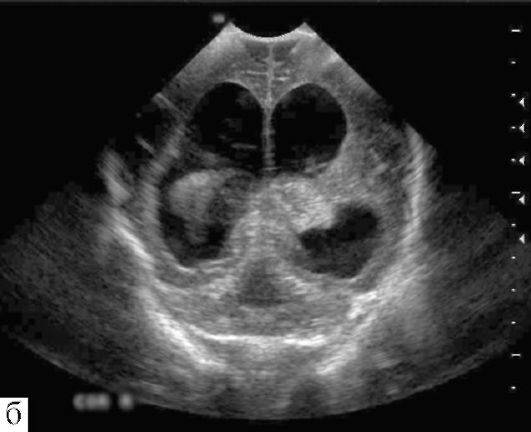

УЗИ проходит благодаря воздействию звуковых волн с настолько высокой частотой, что человеческое ухо не может их воспринимать. При проникновении через организм человека происходит отражение эхо-сигналов с различными скоростными параметрами. Диагностируются процессы, происходящие внутри тела человека.

Часто при обследовании применяется ультразвуковая методика под названием нейросонография, которая с высокой точностью определяет размеры отдельных участков головы, наличие различных аномалий, раковых образований.

Особенности ультразвукового обследования сосудов головного мозга

При выполнении УЗИ доктор способен узнать структуру исследуемого сосуда, принять решение о функциональной способности, наличии патологических отклонений, дефектах. Метод диагностики носит название: допплерография.

Процедура делится на три вида:

Стандартная форма, которая выглядит, как двухплоскостное обследование – способ дает возможность произвести полноценное исследование, изучив сосуды до места их попадания в каналы, заметив новообразования.

Дуплексная форма – результаты сканирования (отображение сосудистой системы головного мозга) выдаются человеку в образе цветного изображения. Врач имеет детальную картину как внечерепной, так внутричерепной структуры, что кардинально упрощает определение диагноза.

Трехмерное ультразвуковое обследование позволяет создать сопоставимое по информативности с фотографическим отображение сосудов для дальнейшего анализа состояния верификации структурных нарушений. Имеется один минус, который не позволит врачу добиться получения данных о функциональном состоянии кровоснабжения.